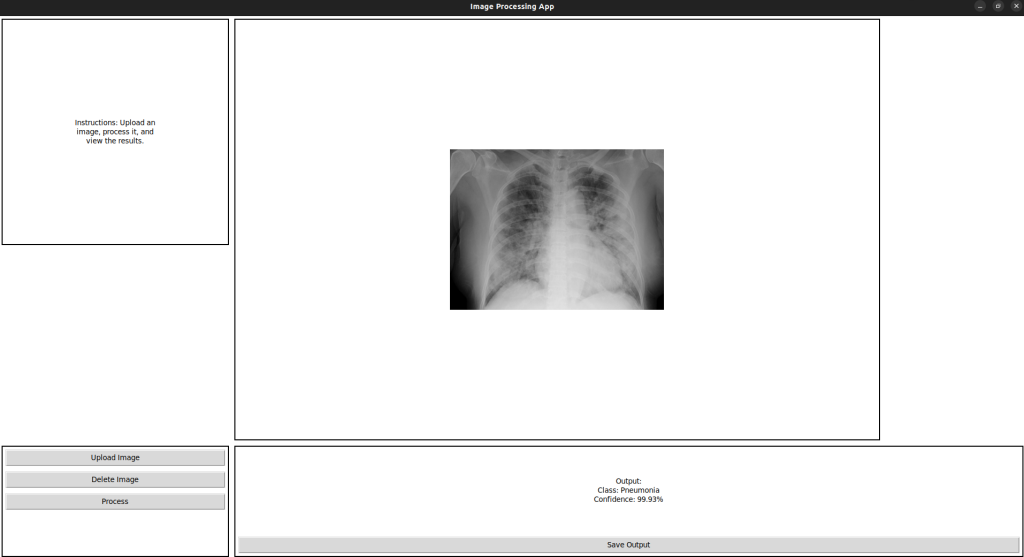

طراحی سامانه کمک یار تشخیص پنومونی (عفونت ریه)

– آموزش مدل مورد نظر بر اساس عکس های رادیولوژی

– تشخیص پنومونی

– بهبود صحت و دقت به صورت بازگشتی

– قابلیت کارکرد بر روی عکس های دلخواه

– سطح اطمینان بالای ۹۵ درصد